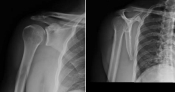

What’s the diagnosis? @emdaily.cooperhealth.org